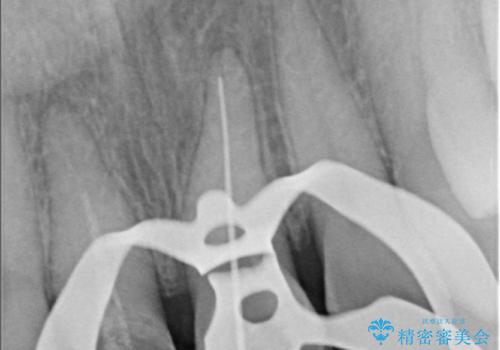

- 気を失って転倒し、前歯をぶつけたことをきっかけに「かかりつけ医で抜歯と診断された」との主訴で来院された患者様です。

レントゲン撮影や顕微鏡下での精査、メチレンブルーによる染色検査を行った結果、破折線は認められず、保存可能と判断しました。